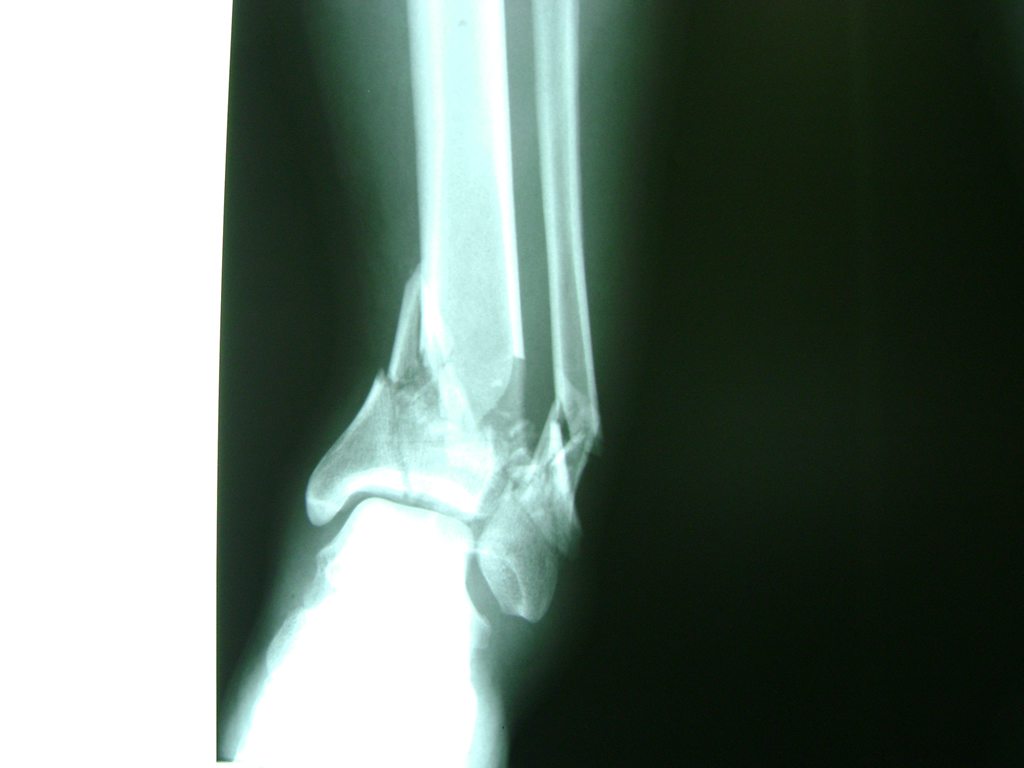

Una fractura de tobillo es la rotura de uno o más de los huesos del tobillo. Estas fracturas pueden ser:

- Parciales (el hueso está sólo parcialmente fisurado, no del todo).

- Completas (el hueso está perforado y está en 2 partes).

- Producirse en uno o ambos lados del tobillo.

Algunas fracturas de tobillo pueden requerir cirugía si:

- Los extremos de los huesos están desalineados entre sí (desplazados).

- La fractura se extiende hasta la articulación del tobillo (fractura intra-articular).

- Los tendones o ligamentos (tejidos que sujetan los músculos y los huesos entre sí) están rotos.

- El médico cree que sus huesos probablemente no sanen apropiadamente sin cirugía.

- El médico considera que la cirugía puede permitirle una recuperación más rápida y confiable.

- En los niños, la fractura involucra la parte del hueso del tobillo donde el hueso está creciendo.